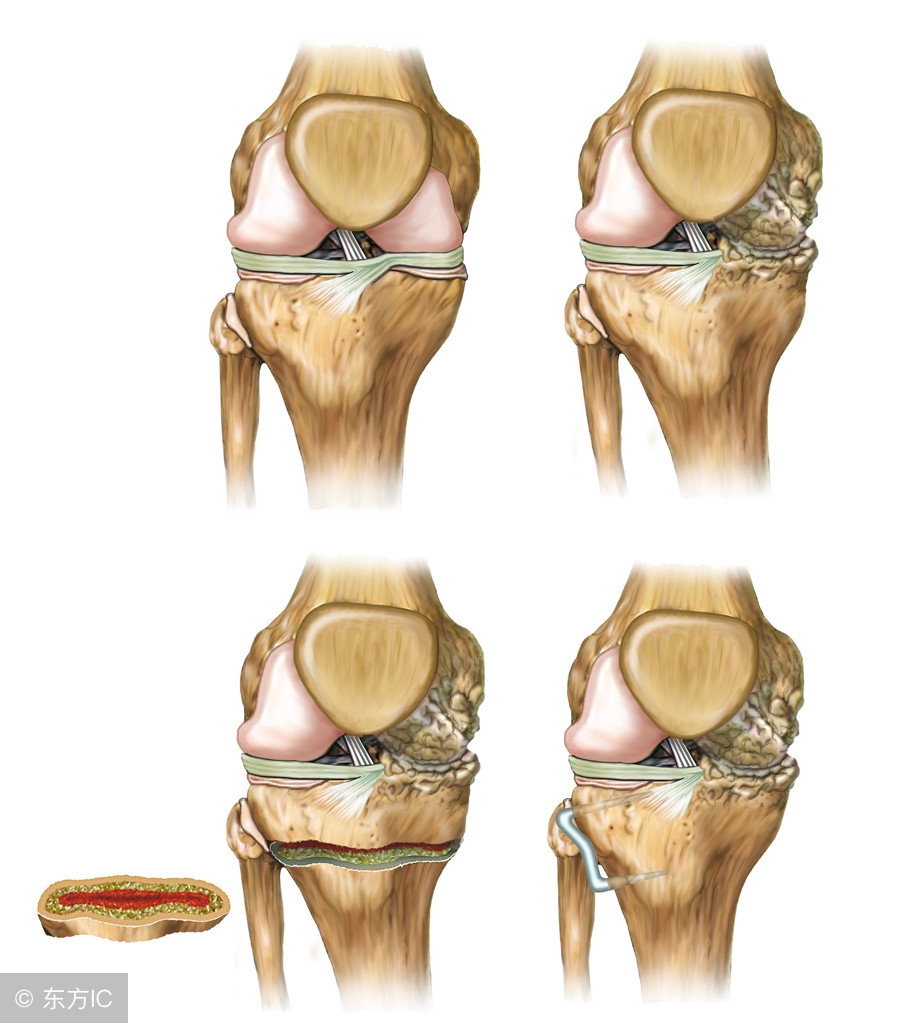

诊断骨关节炎主要靠拍片子, 拿膝关节为例,主要有四个特点: 骨质增生,关节面硬化、关节间隙变窄以及临关节囊性变。

治疗方面一般现在主张按阶梯治疗,能保守就保守,比如改变不良习惯,锻炼股四头肌,口服非类消炎药。保守治疗效果无效,或病情进行性加重,考虑关节镜清理甚至关节置换手术。